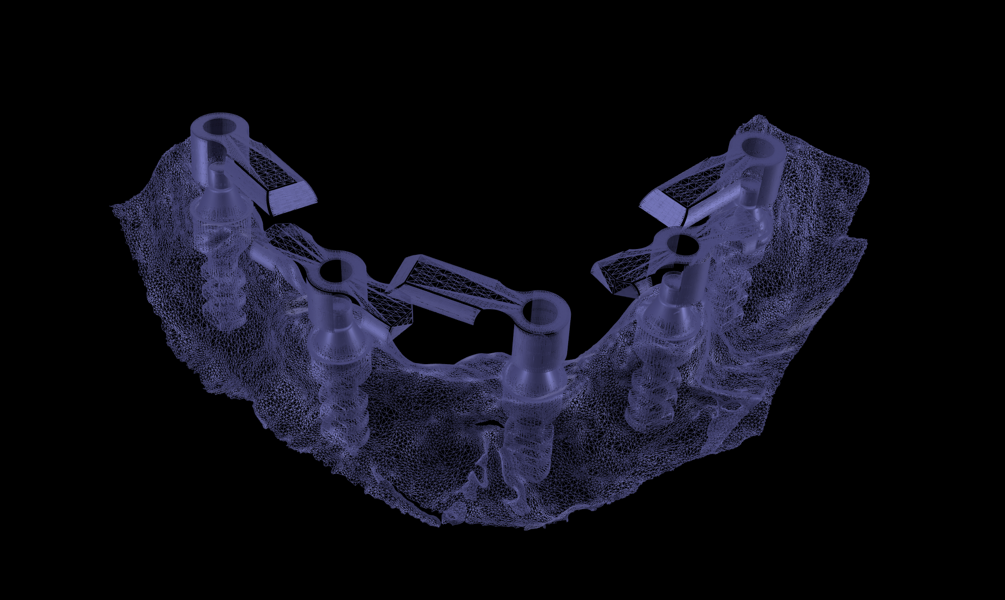

Figs. 3a & b: Segmented CBCT scan (a). Mandibular arch morphology after virtual teeth extractions (b).

Intra-oral examination revealed compromised mandibular dentition, an old fixed prothesis, missing posterior teeth on the left side, periodontal involvement and gingival inflammation. A panoramic radiograph was obtained, and the findings were reported to the patient (Figs. 1a & b; 2a & b). Both mandibular canines had visible periapical radiolucencies. A CBCT scan was performed for a more detailed assessment of the alveolar bone anatomy (Figs. 3a & b). Temporomandibular joint examination revealed no indication of dysfunction (crepitus, clicking or pain).